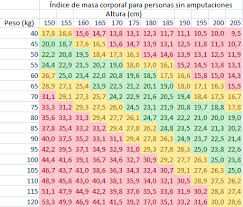

678 × 518 - gimolimpo.com

{"cb":15,"id":"jpp4X3OVBi6CfM:","isu":"gimolimpo.com","itg":0,"ity":"jpg","oh":518,"ou":"http://www.gimolimpo.com/PAGINA%2040/Castup_tv%20-%20The%20largest%20streaming%20platform%20for%20live%20streaming%20,%20live%20broadcasting%20and%20more___archivos/fondo_dieta_3.jpg","ow":678,"pt":"fondo_dieta_3.jpg","rid":"fqzWY27NIw7kDM","rmt":0,"rt":0,"ru":"http://www.gimolimpo.com/PAGINA%2040/INDICE%20MASA%20CORPORAL.htm","s":"Se

considera que una persona tiene un peso normal cuando tiene un índice

de masa corporal inferior a 25, entre 20 y 24 para las mujeres y entre

20 y 25 para

...","sc":1,"th":196,"tu":"https://encrypted-tbn0.gstatic.com/images?q\u003dtbn:ANd9GcTNxN-cKcd-O4XYTNYStZff7LMytZn8CAb7XGv9aZCsd9KEqRF4vw","tw":257}

350 × 225 - gimolimpo.com

{"id":"eD7cRRkVLMiQpM:","isu":"gimolimpo.com","itg":0,"ity":"jpg","oh":225,"ou":"http://www.gimolimpo.com/PAGINA%2029/Tabla_IMC.jpg","ow":350,"pt":"gim

olimpo","rid":"PDBNppOb_qodpM","rmt":0,"rt":0,"ru":"http://www.gimolimpo.com/PAGINA%2029/I%20M%20C.htm","s":"Hoy

habia 451 Visitantes (2439 número de aciertos) ¡Aqui en esta

página!","sc":1,"th":180,"tu":"https://encrypted-tbn0.gstatic.com/images?q\u003dtbn:ANd9GcQ4hZv433jUY5siYozITKpARz0jX6WrzceI_YJgTLwkbHfpdYGD","tw":280}